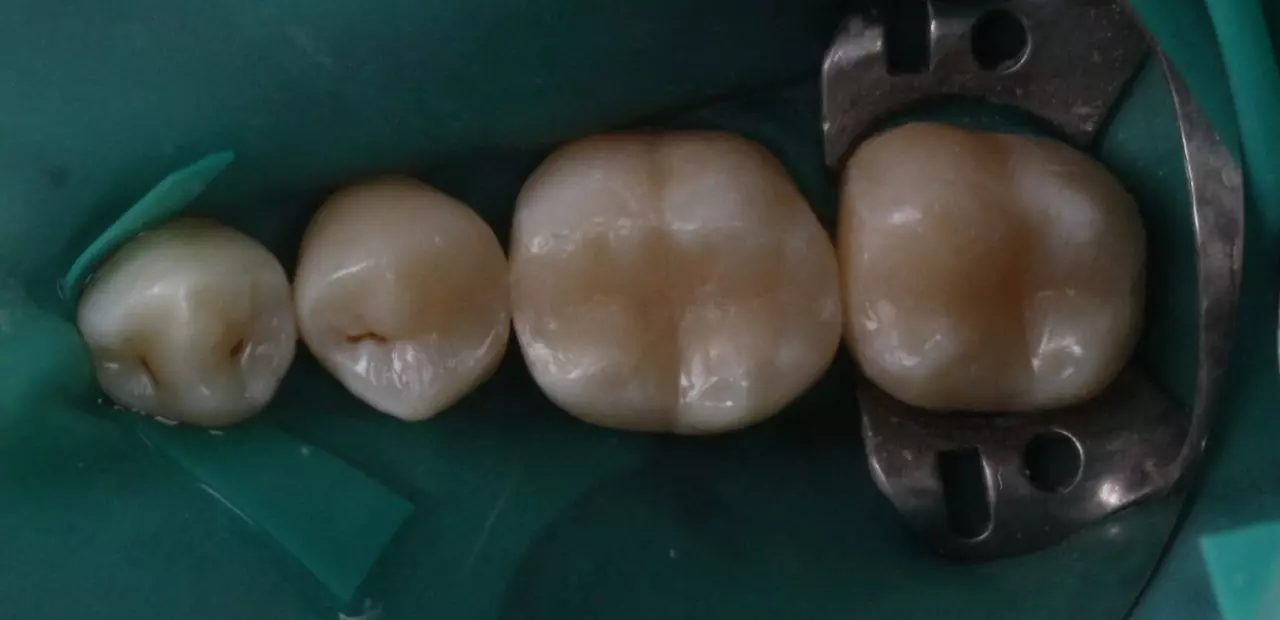

Лікування вторинного карієсу 45.46.47.